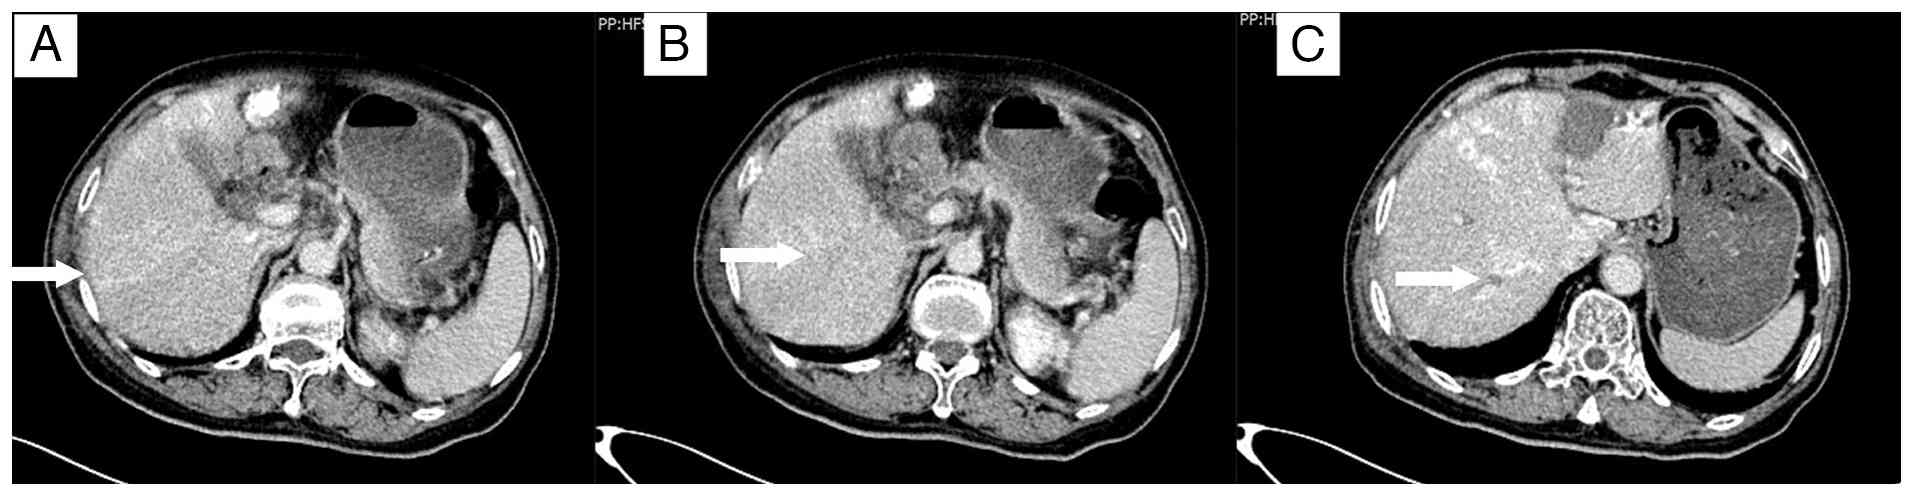

Enhanced computed tomography scans

following transarterial chemoembolization. (A) The lesion beneath

the liver capsule in the right lobe shows no significant reduction

in size compared with before, with mild enhancement (arrow). (B)

The lesion adjacent to the portal vein in the right lobe still

shows mild enhancement (arrow). (C) The lesion at the apex of the

right lobe of the liver shows no significant reduction in size

compared with before, with mild enhancement (arrow).

Figure 4.

Enhanced computed tomography scans following transarterial chemoembolization. (A) The lesion beneath the liver capsule in the right lobe shows no significant reduction in size compared with before, with mild enhancement (arrow). (B) The lesion adjacent to the portal vein in the right lobe still shows mild enhancement (arrow). (C) The lesion at the apex of the right lobe of the liver shows no significant reduction in size compared with before, with mild enhancement (arrow).

A total of 5 days after the initial chemotherapy treatment, the patient was admitted to the in the Department of Hepatobiliary Surgery and underwent RFA with a concurrent biopsy of the left hepatic lobe lesion. The postoperative pathology, performed as aforementioned, confirmed liver metastasis of colorectal cancer. The cells were arranged in irregular glandular structures with infiltrative growth, and the nuclei were enlarged, with prominent nucleoli (Fig. 3A). The patient developed abdominal pain and a fever following the operation. A CT scan 1 week after RFA revealed signs of infection (Fig. 3B and C), which recovered after antibiotic treatment. In October 2013, the chemotherapy regimen was switched to XELOX (1,500 mg capecitabine orally twice daily on days 1–14; 180 mg oxaliplatin by intravenous infusion on day 1), followed by TACE 8 days later, targeting the metastatic lesions in the right hepatic lobe. A contrast-enhanced CT scan conducted 10 days post-TACE showed no significant reduction in the size of the three lesions in the right hepatic lobe compared with the size in the images taken before the procedure, with persistent mild enhancement (Fig. 4).